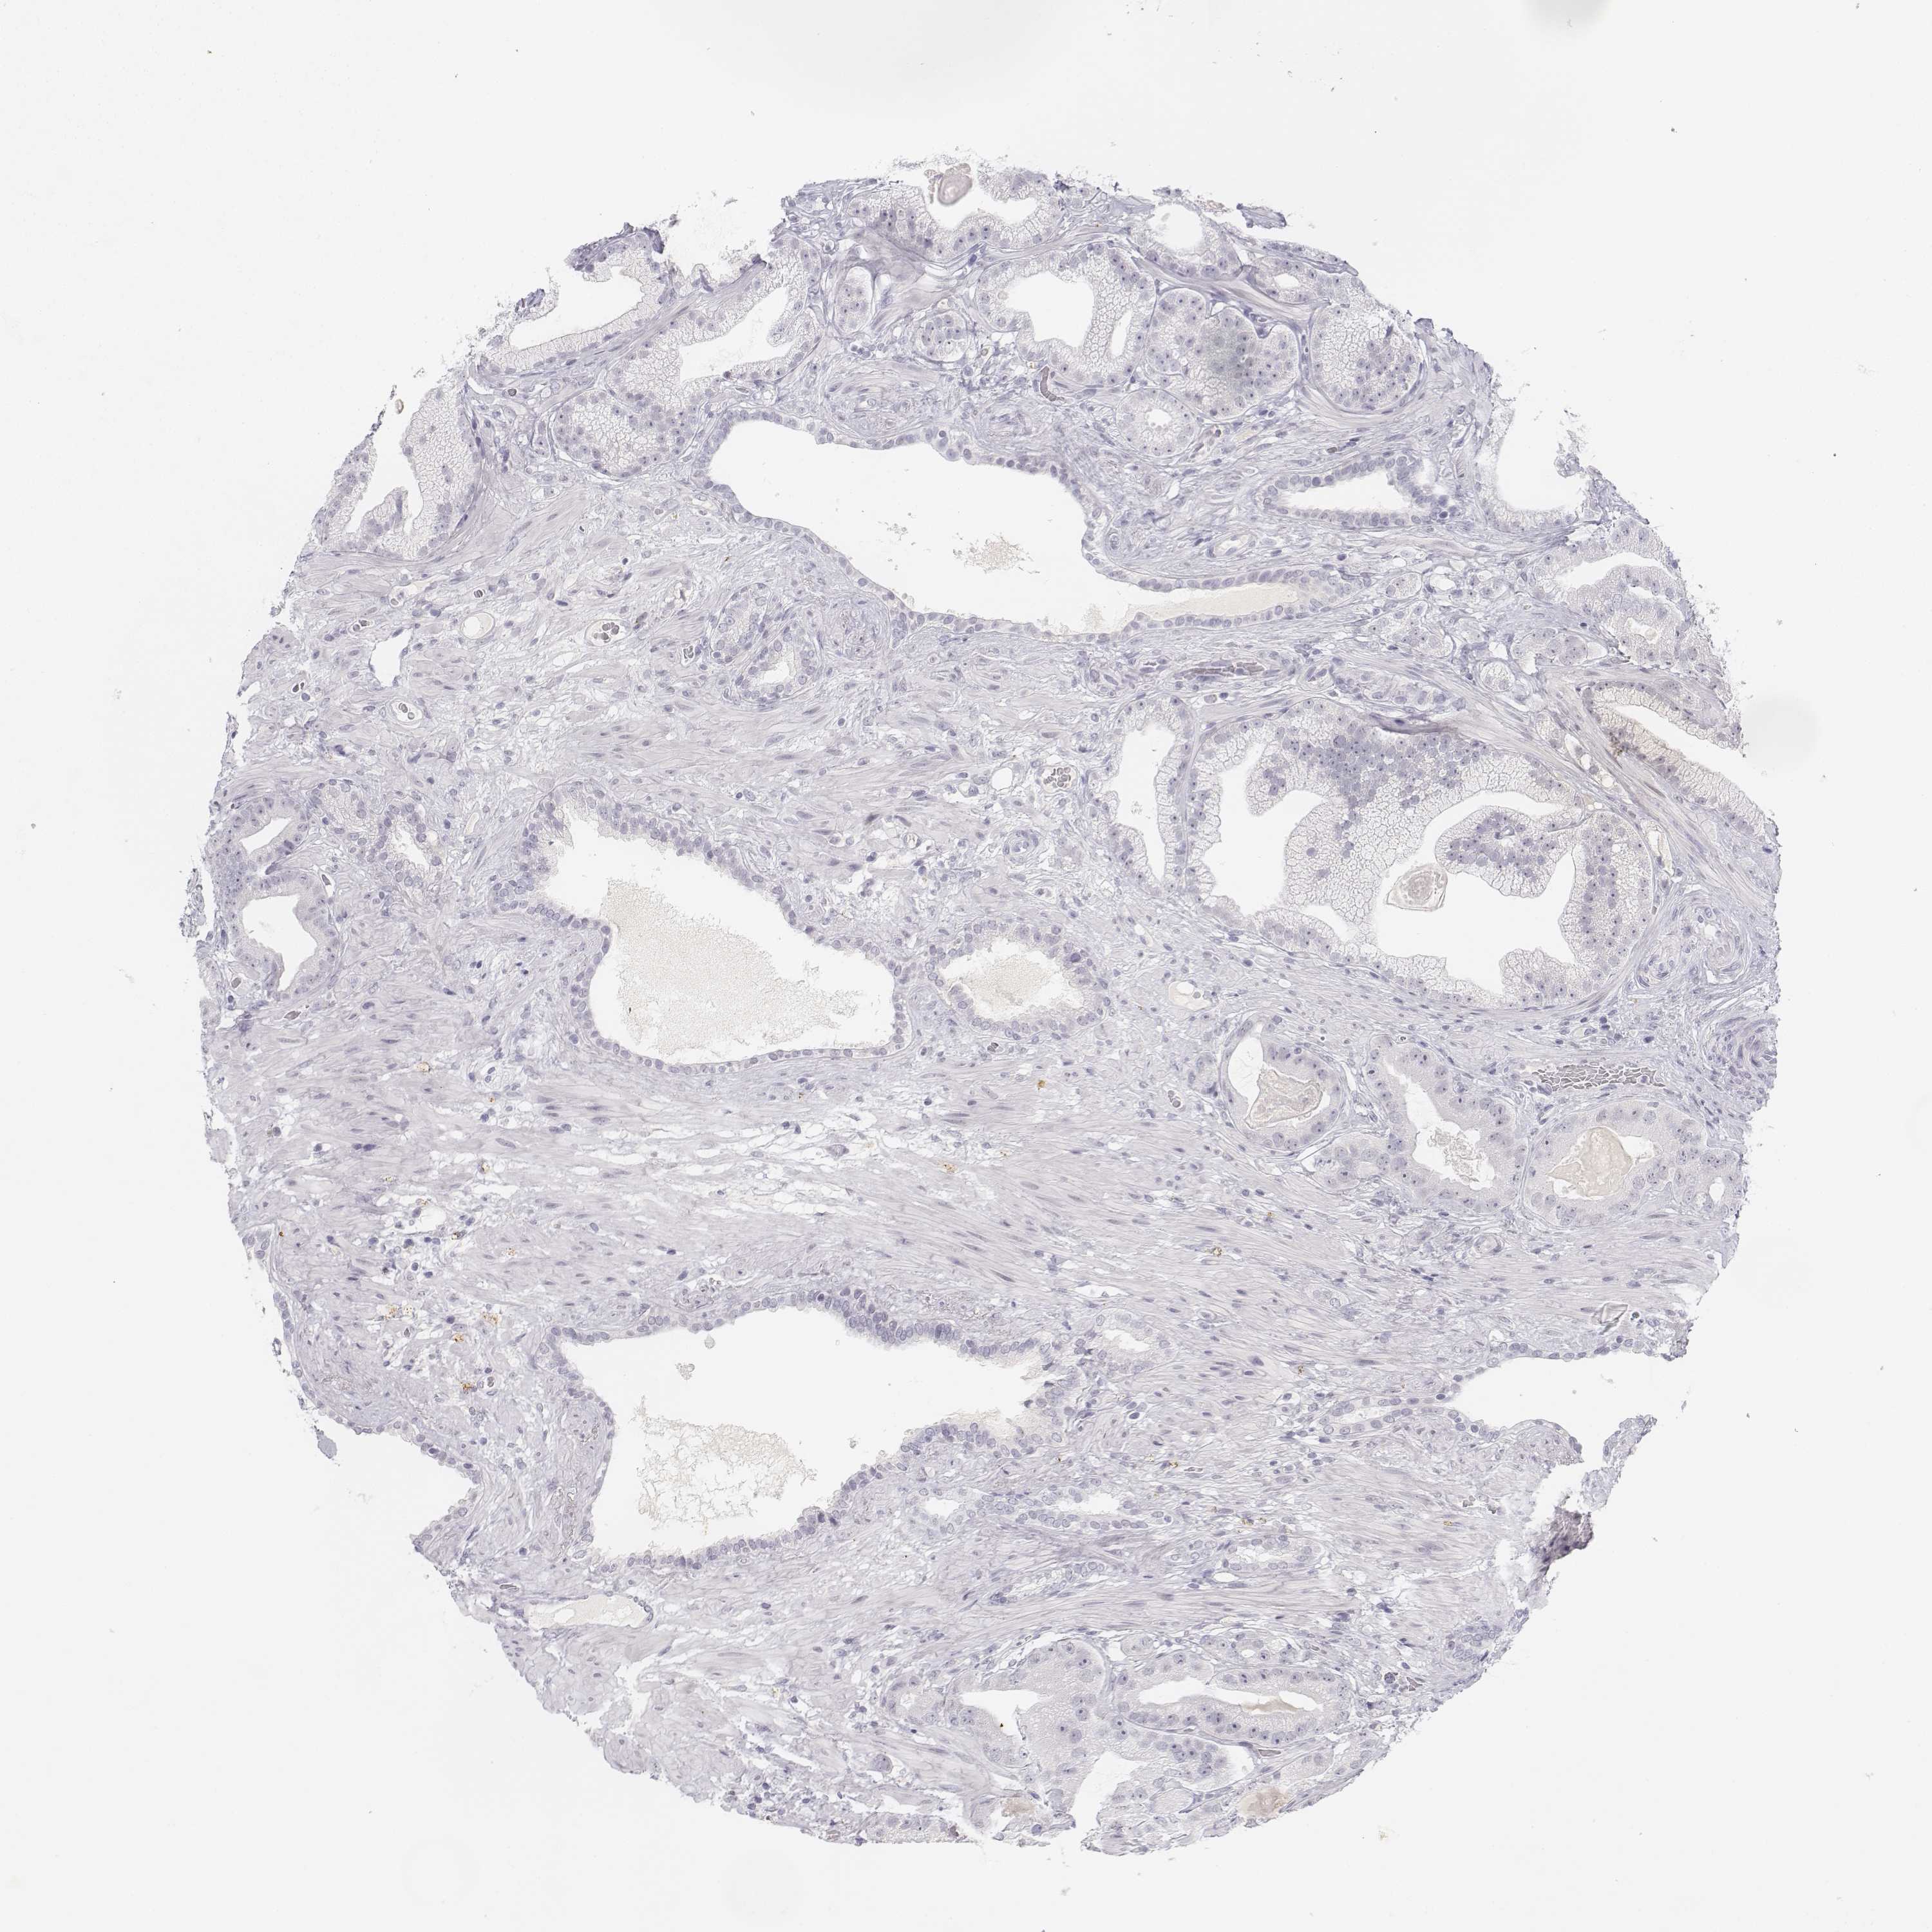

PROSTATE CANCER - Protein expressioni

A mouse-over function shows sample information and annotation data. Click on an image to view it in a full screen mode. Samples can be filtered based on level of antibody staining by selecting one or several of the following categories: high, medium, low and not detected. The assay and annotation is described here.

Note that samples used for immunohistochemistry by the Human Protein Atlas do not correspond to samples in the TCGA dataset.

Antibody stainingi

Antibody staining in the annotated cell types in the current human tissue is reported as not detected, low, medium, or high, based on conventional immunohistochemistry profiling in selected tissues. This score is based on the combination of the staining intensity and fraction of stained cells.

Each image is clickable and will lead to virtual microscopy that enables deeper exploration of all samples and also displays staining intensity scores, fraction scores and subcellular localization as well as patient and tissue information for each sample.

Antibody HPA039714

Staining

High

Medium

Low

Not detected

Intensity

Strong

Moderate

Weak

Negative

Quantity

>75%

75%-25%

<25%

None

Location

Nuclear

Cytoplasmic/membranous

Cytoplasmic/membranous,nuclear

Adenocarcinoma, High grade

Adenocarcinoma, NOS

Adenocarcinoma, Low grade